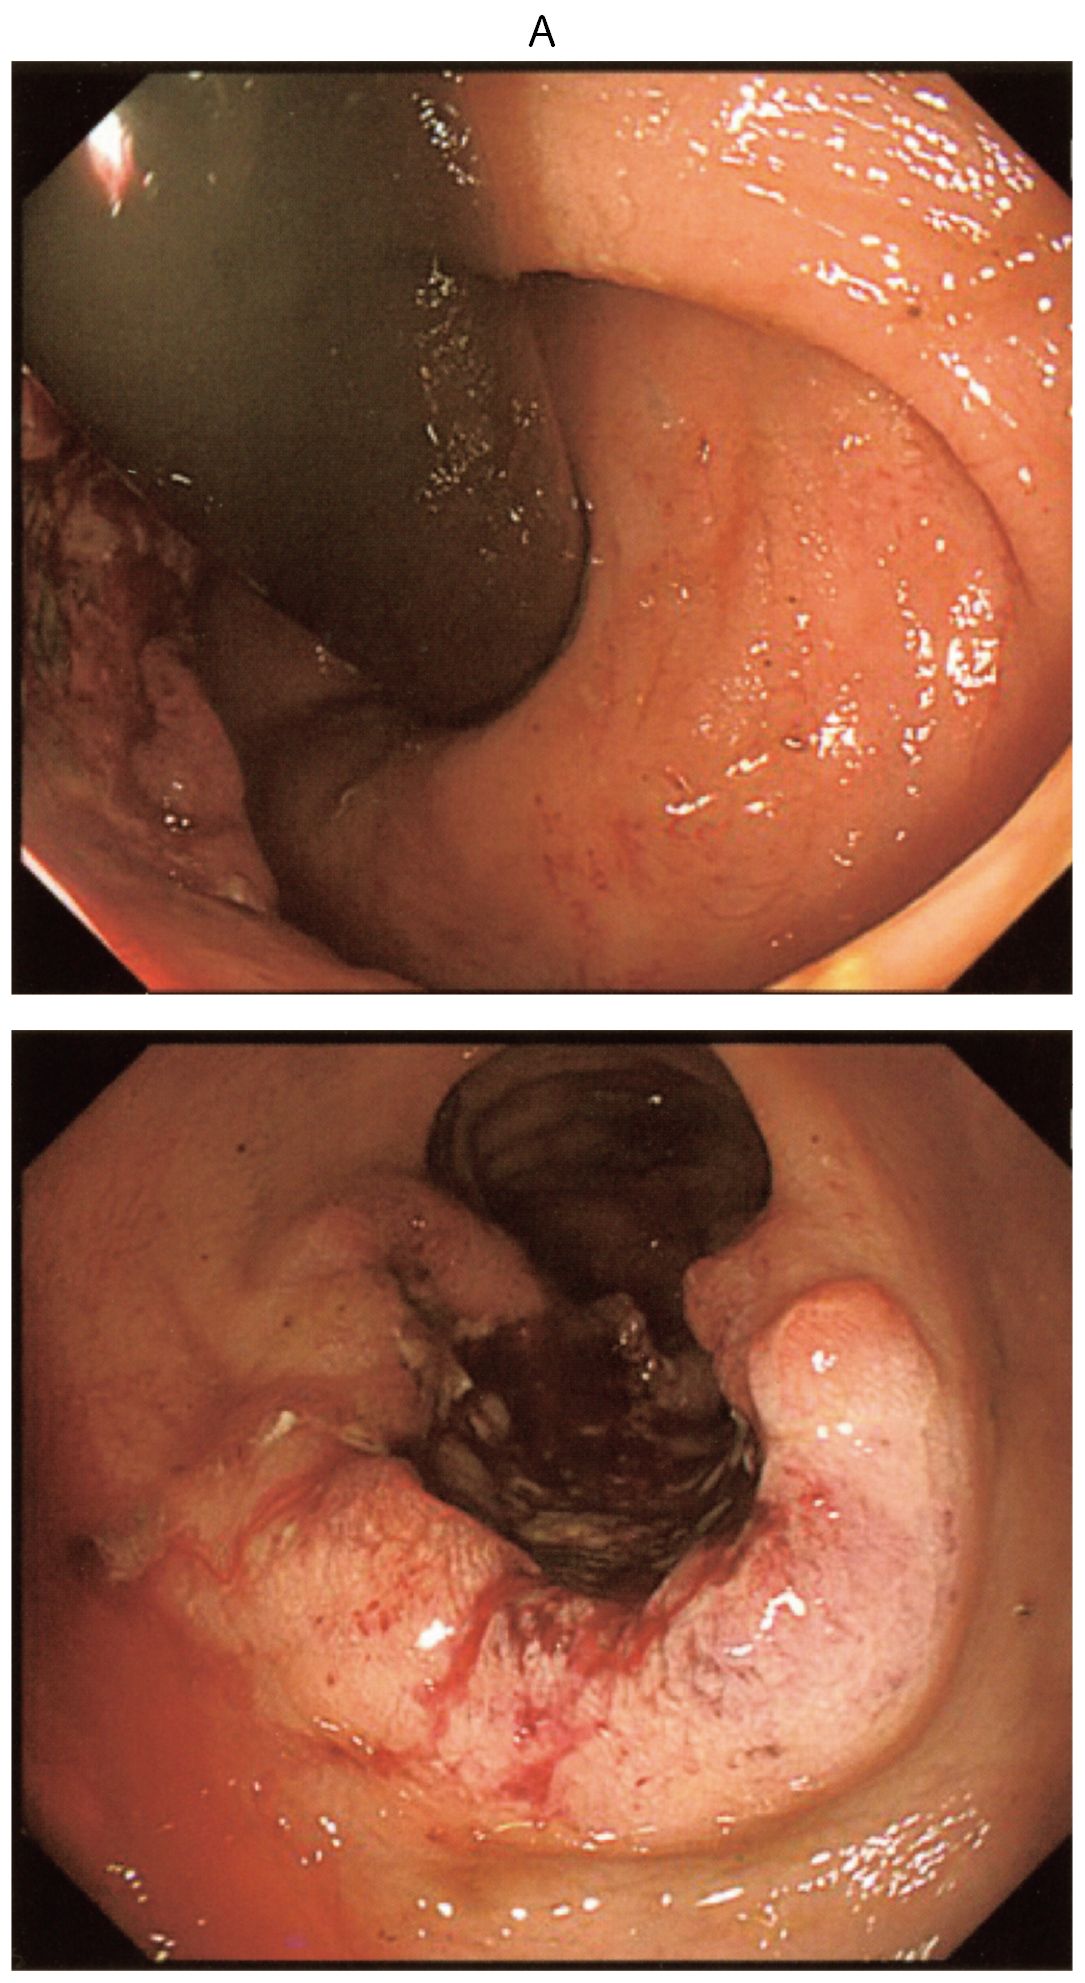

45歳の男性。下血を主訴に来院した。1か月前から排便時の出血を自覚していた。既往歴に特記すべきことはない。喫煙は20本/日を25年間。飲酒歴はない。意識は清明。身長170cm,体重54kg。体温36.4℃。脈拍68/分,整。血圧112/68mmHg。呼吸数12/分。SpO2 96%(room air)。眼瞼結膜と眼球結膜とに異常を認めない。心音と呼吸音とに異常を認めない。腹部は平坦,軟で,肝・脾を触知しない。血液所見:赤血球508万,Hb 15.2g/dL,Ht 45%,白血球6,400,血小板24万。血液生化学所見:総蛋白7.2g/dL,アルブミン4.8g/dL,総ビリルビン1.0mg/dL,直接ビリルビン0.2mg/dL,AST 18U/L,ALT 16U/L,LD 166U/L(基準124~222),ALP 63U/L(基準38~113),尿素窒素12mg/dL,クレアチニン0.8mg/dL,血糖92mg/dL,CEA 10.2ng/mL(基準5以下),CA19-9 32U/mL(基準37以下)。CRP 0.2mg/dL。下部消化管内視鏡検査の直腸像(A)と腹部造影CT(B)とを下に示す。その他画像検査で,遠隔転移は認めなかった。開腹手術を行うことにした。